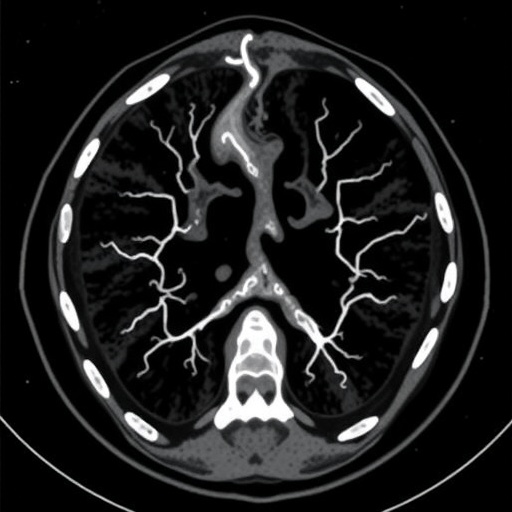

CT angiography has emerged as a preferred imaging modality because of its ability to provide detailed, high-resolution images of blood vessels. Unlike traditional angiography, which is more invasive and involves catheterization, CT angiography employs non-invasive techniques that can swiftly display the anatomy of the vascular structure. The capability to visualize the vascular system in three dimensions adds another layer of analysis that enhances the diagnostic process. However, its effectiveness in measuring flow parameters, especially in dynamic conditions within a phantom model of carotid stenosis, raises essential questions regarding its reliability compared to other standard techniques.

The study employed a sophisticated hemodynamic phantom model simulating carotid stenosis, allowing researchers to replicate various conditions reflecting real-life scenarios. This innovative model facilitated precise measurements of blood flow dynamics, which is critical for validating the performance of the imaging techniques being compared. Through this approach, the researchers aimed to establish correlations between the imaging data obtained from CT angiography and the hemodynamic parameters assessed by duplex sonography. The implications of such findings could enhance clinical decision-making, leading to better patient outcomes and improved management strategies for carotid artery diseases.

As the research delved deeper into the comparative analysis, it became evident that discrepancies exist between the information garnered from both imaging modalities. CT angiography might reveal structural abnormalities and the overall morphology of the arteries but could fall short when it comes to real-time blood flow evaluations. Conversely, duplex sonography excels in capturing hemodynamic variations but may sometimes lack the detailed anatomical precision offered by CT imaging. This duality highlights the necessity for a balanced approach in utilizing both techniques in clinical practice to achieve a comprehensive assessment of carotid stenosis.